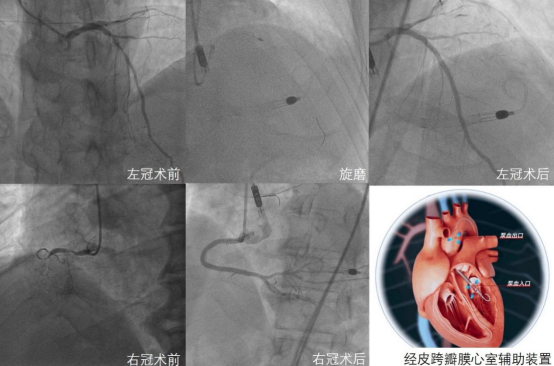

术中,心血管团队经左股动脉置入国产经皮跨瓣膜心室辅助装置。首先,在团队研发的冠状动脉CTA人工智能可视化系统指导下,开通慢性完全闭塞的右冠状动脉并置入支架,之后对左冠状动脉病变进行充分旋磨预处理后完成血运重建。手术历时4小时,患者全程血流动力学稳定。术后即刻撤除经皮跨瓣膜心室辅助装置,患者恢复良好,并于术后第三日出院。

术前,哈医大一院心血管团队对患者病情进行系统评估,考虑患者为典型复杂高危病例,术中操作复杂,血流动力学异常可能性大,决定在国产经皮跨瓣膜心室辅助装置支持下为患者行同次完全血运重建。相较于目前临床常用的循环辅助器械主动脉内球囊反搏(IABP),中国自主研发、拥有独立知识产权的国产经皮跨瓣膜心室辅助装置可提供更好的血流动力学支持,稳定全身重要脏器的血供;与体外膜肺氧合(ECMO)相比,经皮跨瓣膜心室辅助装置可降低心脏负荷,改善心肌对氧的供需平衡,促进心脏恢复。